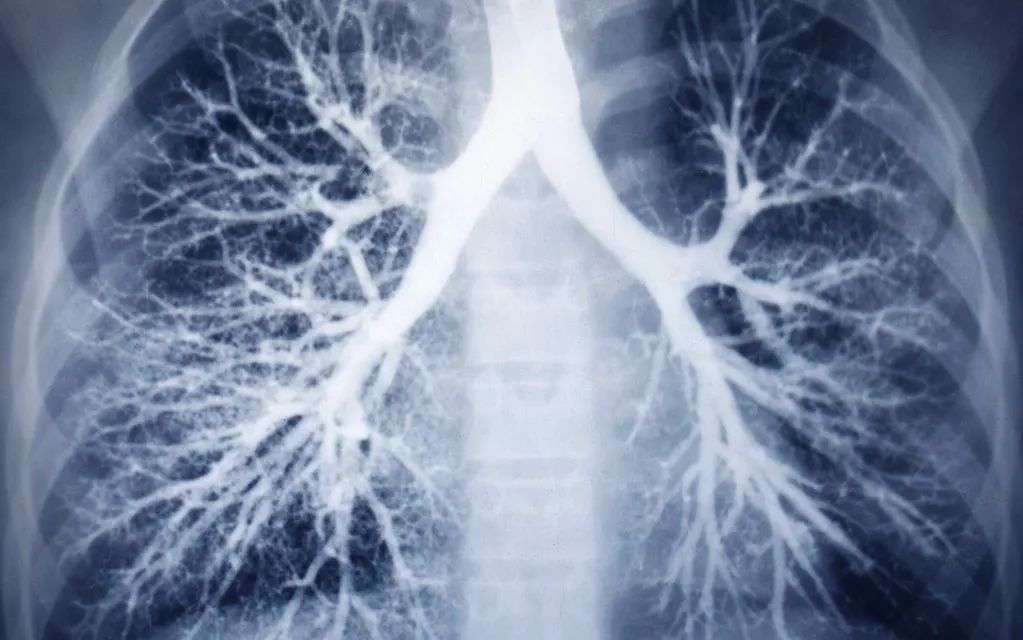

患肺炎后,胸部CT可表现为多种形式,通常会有斑片状、磨玻璃、网格状等阴影,需要医生根据具体影像判断。

感染新冠后,病毒细菌等病原体仅累及上呼吸道时,通常会出现咳嗽,CT检查没有肺炎症状;当炎症累及下呼吸道,就可能发展成肺炎。

CT/X光检查 | 肺纹理清晰 | 有阴影 |